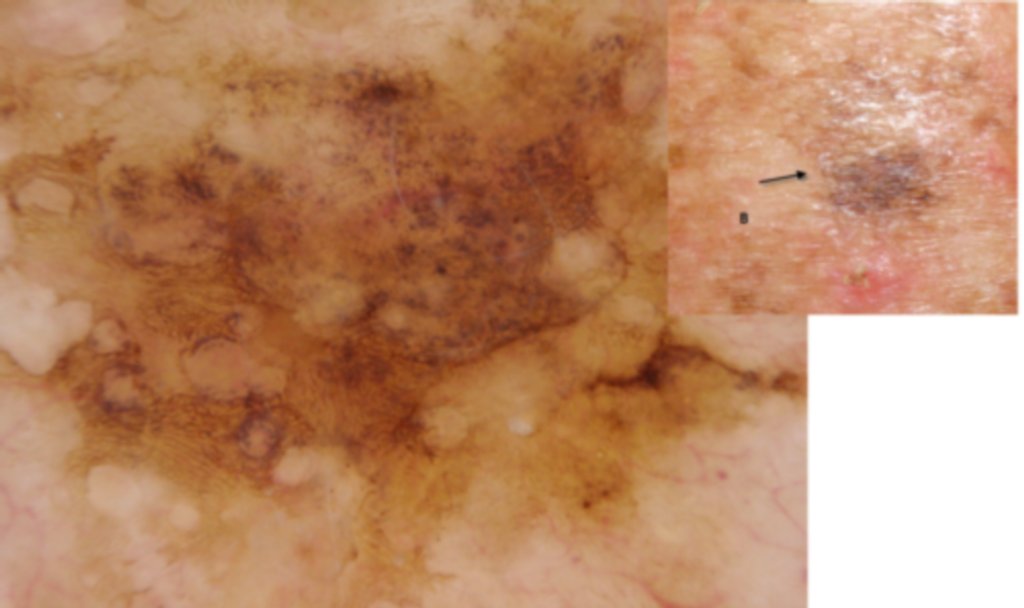

Diagnosis: Solar lentigo